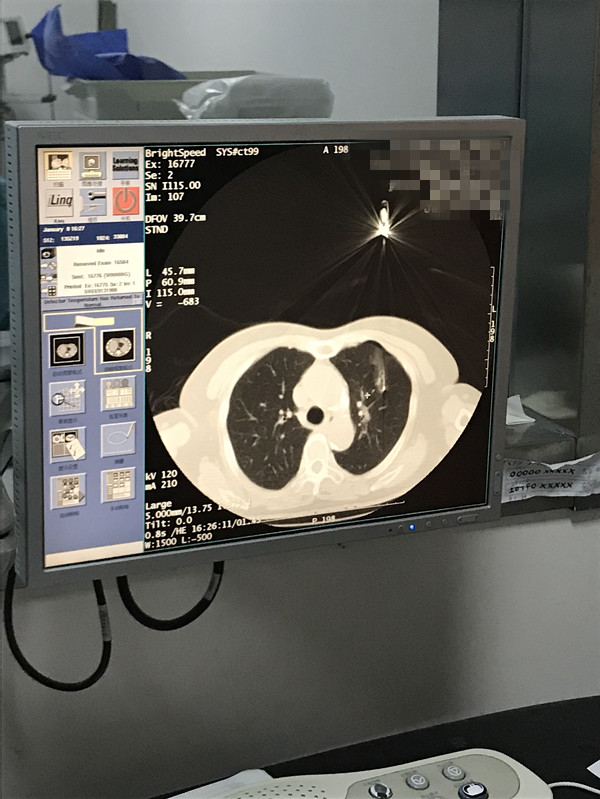

下一篇:2021年1月份肺部氩氦刀手术